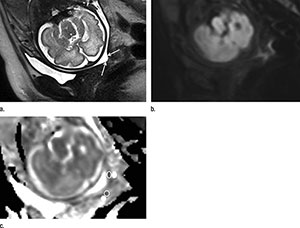

To learn more, Dr. Masselli and colleagues used an MRI technique called diffusion-weighted imaging (DWI) to examine pregnant women who had been referred for suspected fetal or placental abnormality. DWI reveals differences in the mobility of water molecules in tissue and the results can be used to create apparent diffusion coefficient (ADC) maps that provide a measure of local cell density. DWI has been increasingly used for abdominal and pelvic diseases, but has not been tested for the evaluation of the uterine cervix in pregnant patients.

Of the 30 women, eight, or 27 percent, delivered within a week of the MRI examination. The other 22 delivered an average of 55 days later. The researchers compared differences in ADC values at MRI between two areas of the cervix: the inner, subglandular zone and the outer, stromal area. While stromal ADC and sonographic cervical length showed no difference between both groups, the subglandular ADC was higher in patients with impending delivery, suggesting an increased mobility of water molecules in that area consistent with cervical ripening.